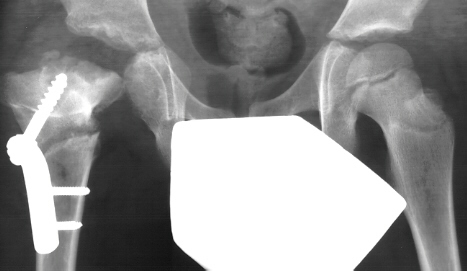

- Age 6: Valgus osteotomy for subluxation and 2cm leg length inequality.

- Age 15: Valgus osteotomy for hip incongruity.

- Age 20: Hip arthroscopy. Hip fusion recommended.

This case is an example of untreated septic arthritis which caused avascular

necrosis of the proximal femur. The primary cause of this is undrained

septic hip. Repeated aspiration is not adequect treatment of a septic hip.